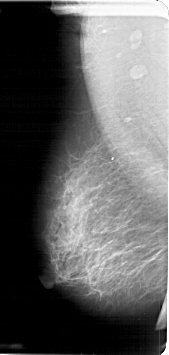

A_1258_1.LEFT_MLO

LESION_TYPE MASS SHAPE IRREGULAR MARGINS SPICULATED

ASSESSMENT 5

SUBTLETY 4

PATHOLOGY MALIGNANT

LESION_TYPE CALCIFICATION TYPE PLEOMORPHIC DISTRIBUTION CLUSTERED

ASSESSMENT 4